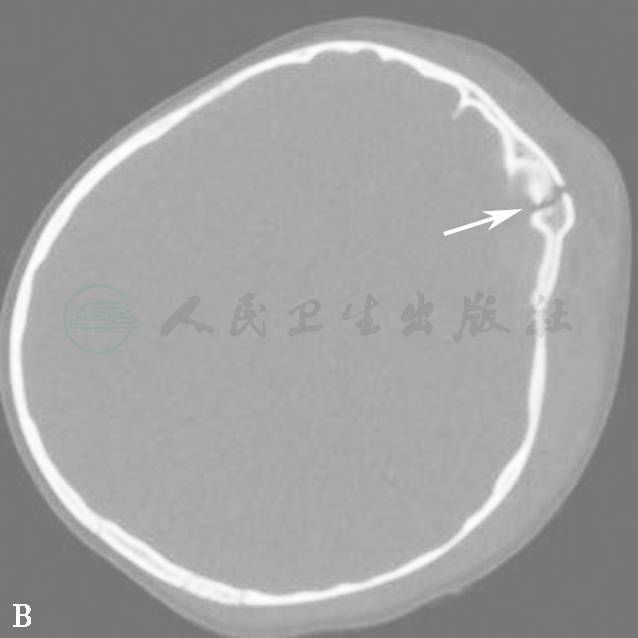

图15  外伤后颅内出血(箭)

A.脑组织窗;B.骨窗;C.VR重建